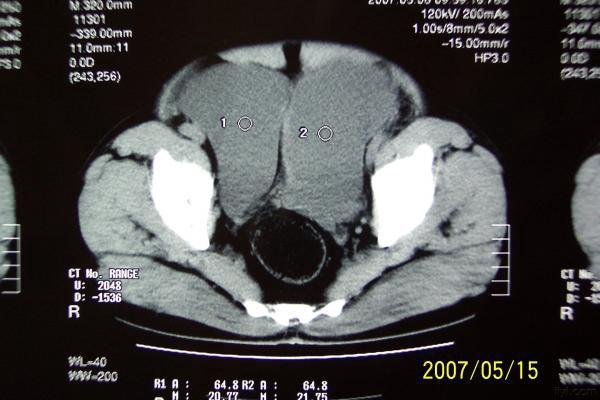

分享下一例巨大膀胱憩室的图片

分享下一例罕见病历的图片,这是我遇到的最大巨大膀胱憩室。